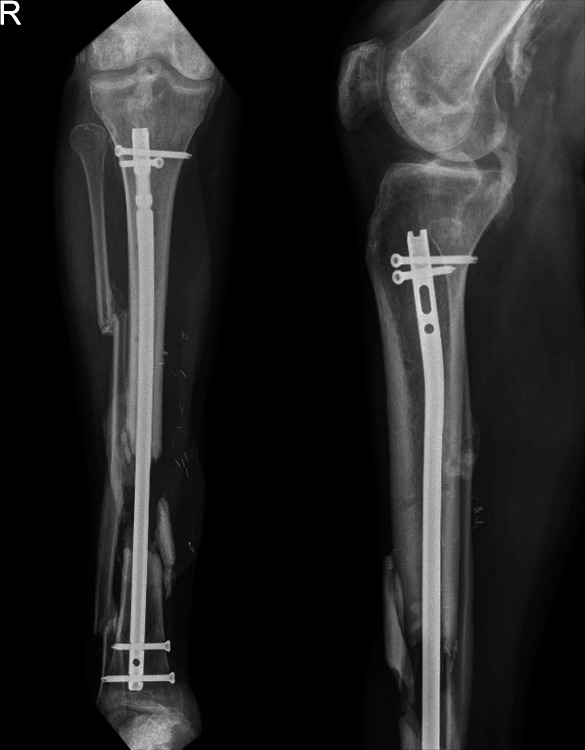

Aim: We present a case where the proximal end of a cannulated tibial nail was inaccessible for removal.

Background: Some common techniques for the removal of broken hardware are discussed in the literature, but there is no one technique that will work in every situation. Routine removal techniques may not suffice when removing a buried or broken tibial nail.

Case description: Difficulties were encountered removing a tibial nail which was deeply sunk into the proximal tibia from its entry point. Therefore, the fracture site was exposed, and the nail was cut. The proximal portion was removed in a retrograde fashion. Removing the distal end of the nail posed a dilemma after standard techniques failed, but it was successfully extracted by threading a Schanz pin into the exposed cannulated portion of the nail and then backslapping a T-handle.

Conclusion: This is a novel technique for the removal of an incarcerated segment of a cannulated tibial nail from the distal tibia when other techniques were unsuccessful.

Clinical significance: The novel method presented in this case report allows for extraction of a sunken tibial intramedullary nail when extractor seating is difficult to obtain and the incarcerated distal segment of a cannulated tibial nail cannot be removed by standard techniques.